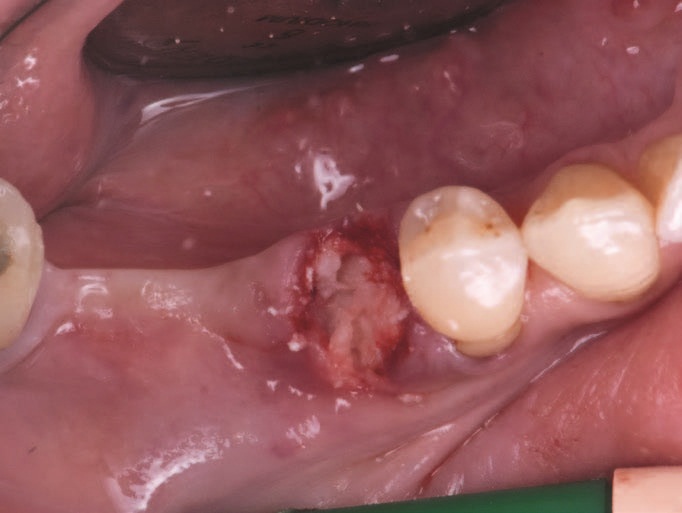

Рис. 4 – Пост-екстракційна лунка.

Пацієнт звернувся до хірурга з мостом у правій задній дузі для реабілітації зубів з 4.5 до 4.8 включно. Зуб 4.5 показав карієс кореня, що зробило його непридатним для підтримки містка. Потім було заплановано видалення зуба 4.5, а також виконання процедури збереження гребеня на постекстраційній лунці для того, щоб у майбутньому здійснити протезування на імплантатах.

Пацієнт пройшов звичайну антибіотикопрофілактику, а старий протез був вилучений шляхом мезіального відділення до зуба 4.8. Потім був вилучений зуб 4.5, і безлоскутно, лунку заповнили кістковою пастою Activabone без регідратації. При контакті з кров’ю кісткова паста вбирала її і набувала формувальну текстуру, що полегшувало заповнення лунки.

Потім поля прищепленої пост-екстракційної лунки стабілізували хрестиком, використовуючи нерозсмоктуючий шовний матеріал (Vicryl 4-0). Через 6 місяців реабілітація пацієнта передбачала встановлення двох остеоінтегрованих імплантатів для підтримки протеза на трьох зубах. Одночасно із встановленням імплантатів проводилася біопсія кістки із регенерованого кісткового об’єму.